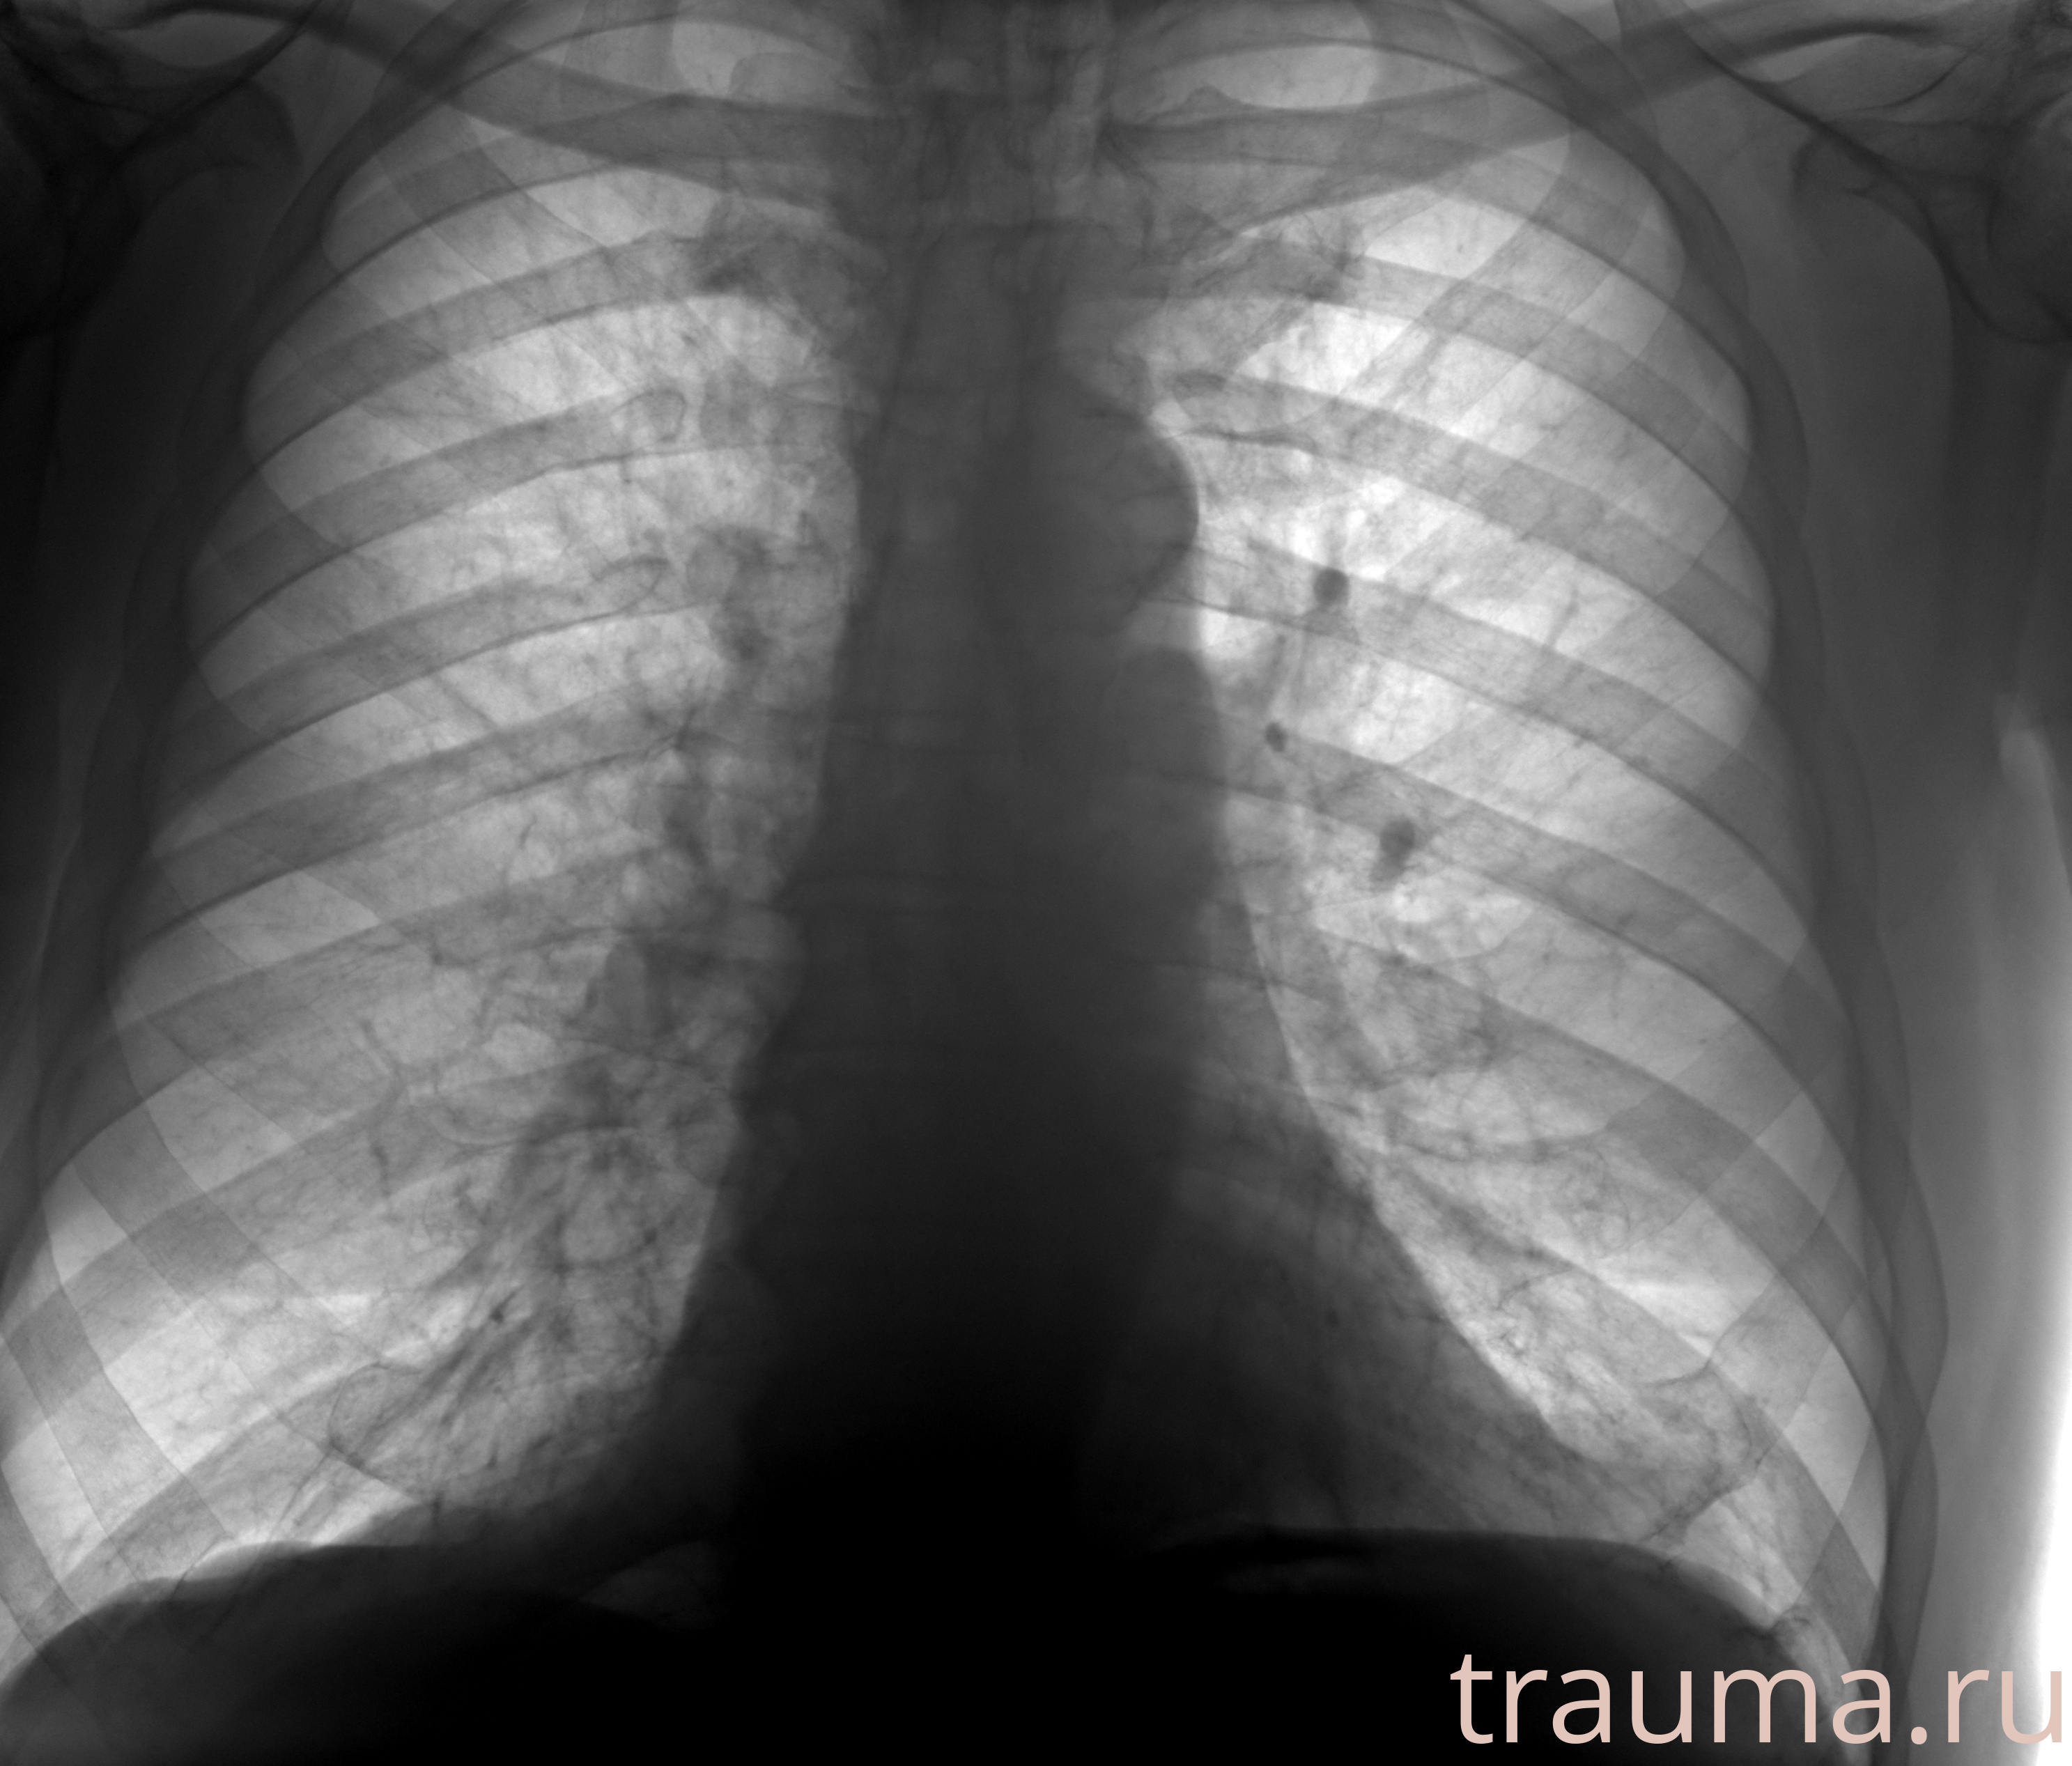

Рентгенограммы

Рентген на дому: по вашему адресу приезжает врач-рентгенолог, травматолог-ортопед с мобильным рентгеновским аппаратом, проводит диагностику травмы или заболевания, делает необходимые рентгенограммы, дает рекомендации по дальнейшему лечению. Получить качественные снимки в домашних условиях возможно благодаря уникальной методике, разработанной МосРентген Центром для института  Склифосовского

Яркость: 1   Контраст: 1   Инвертировать: 0 Увеличение: 1

Перетаскивайте мышь вверх/вниз для контраста, влево/право для яркости. Прокрутка колесом изменяет масштаб. Нажмите Сбросить для возврата к исходному изображению. При увеличении держите мышь в той области, которую хотите рассмотреть.